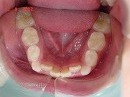

矯正前 正面 矯正前 下顎

矯正後 正面 矯正後 下顎

症例写真の様な方でも、1年6カ月で当院独自の方法により、

改善していく事が可能です。